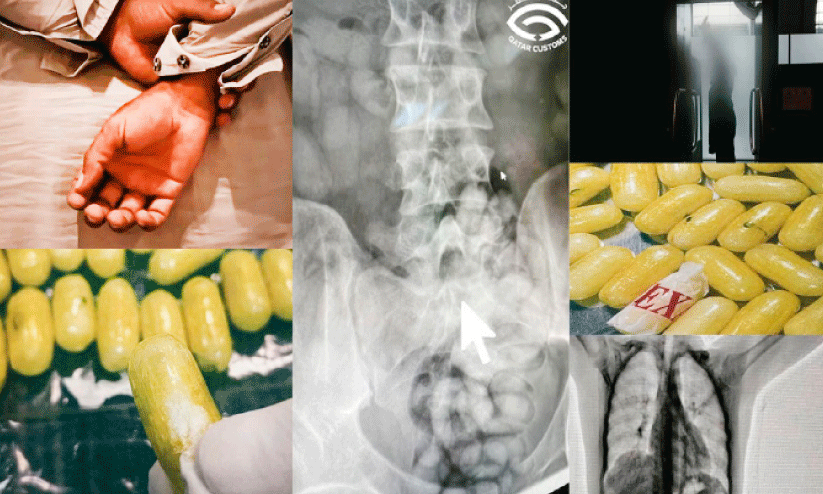

ദോഹ: ഗുളിക രൂപത്തിൽ ലഹരിമരുന്ന് വിഴുങ്ങിയെത്തിയ യാത്രക്കാരനെ ഹമദ് അന്താരാഷ്ട്ര വിമാനത്താവളത്തിൽ പിടികൂടി. പ്രത്യേകം ക്യാപ്സൂളുകളുടെ മാതൃകയിലാക്കി വിഴുങ്ങി, ശരീരത്തിനുള്ളിൽ ഒളിപ്പിച്ചെത്തിയ യാത്രക്കാരനെ സംശയം തോന്നിയതിനെ തുടർന്ന് നടത്തിയ പരിശോധനയിലാണ് മയക്കു മരുന്ന് കണ്ടെത്തിയത്. സംശയത്തെ തുടർന്ന് യാത്രക്കാരനെ ബോഡി സ്കാനർ പരിശോധനക്ക് വിധേയമാക്കുകയായിരുന്നു. കൂടുതൽ ചോദ്യം ചെയ്യലിനെത്തുടർന്ന് വൈദ്യപരിശോധനക്ക് വിധേയമാക്കിയപ്പോൾ കുടലിൽനിന്ന് 80-ഓളം നിരോധിത ഗുളികകൾ കണ്ടെത്തി. 610 ഗ്രാം വരുന്ന ഷാബുവും ഹെറോയിനുമാണ് അധികൃതർ പിടിച്ചെടുത്തത്. വിഡിയോ ദൃശ്യങ്ങൾ കസ്റ്റംസ് വിഭാഗം സമൂഹ മാധ്യമങ്ങളിൽ പങ്കുവെച്ചു.